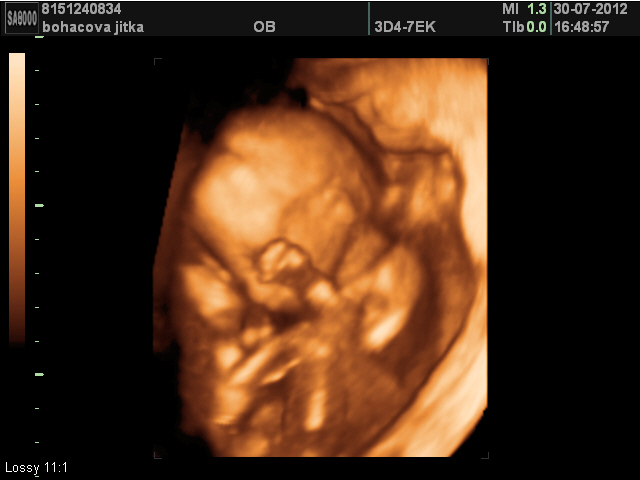

Přikládám 3D fotku naší modelky z 18.týdne :-)